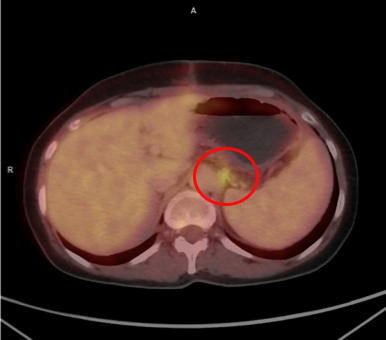

Эпителиальная мезотелиома брюшины, ТxN0M0. Циторедуктивная операция (оментэктомия, париетальная перитонеумэктомия тотальная, экстирпация матки) + HIPEC (цисплатин + доксорубицин) от 08.08.2023. Химиотерапией HIPEC называют новаторскую разновидность лечения злокачественных новообразований. Эта процедура подразумевает прямое воздействие на опухолевые клетки разогретыми химиопрепаратами. Прогрессирование (ПЭТ/КТ от 21.09.2023; до операции ПЭТ/КТ не выполняли): инфильтративное образование с повышенной метаболической активностью РФП по брюшине слева на уровне ножки диафрагмы/ дна желудка (SUVmax — 5,34), SUVmax (Maximum Standardized Uptake Value) — максимальный показатель степени накопления радиофармпрепарата (РФП) в выделенной зоне интереса; метастазы во множественных внутригрудных лимфатических узлах (бронхо-пульмональные слева и справа, парастернальный слева с SUVmax 3,47 — 4,6). Таргетная терапия Регорафенибом (Стиварга) с 23.09.2023 г. по н.вр. (со снижением дозы до 120 мг/сут. с учетом нежелательных явлений — ладонно-подошвенный синдром легкой степени). Частичный регресс (ПЭТ/КТ от 20.12.2023): нивелирование инфильтративного образования с повышенной метаболической активностью РФП по брюшине слева (ранее на уровне ножки диафрагмы дна желудка определялось образование 11х8 мм с SUVmaх — 5,34), снижение в динамике метаболической активности РФП во множественных внутригрудных лимфатических узлах (бронхопульнональный слева с SUVmaх — 3,6, размерами до 8х6 мм, ранее SUVmaх — 4,6; бронхо-пульмональный справа с SUVmaх — 3,56 размерами до 9х7 мм, ранее SUVmaх — 4,3; парастернальный слева с SUVmaх — 1,6 размерами до 5 мм, ранее SUVmaх — 3,47). Полный регресс (ПЭТ/КТ 19.03.2024; 24.03.2025).